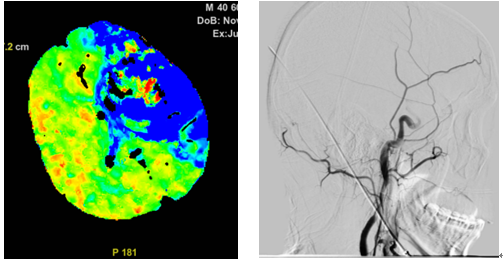

一名 40 岁男性因突发言语不清、右侧肢体无力送至我院急诊。影像检查提示左侧大脑中动脉闭塞,脑组织濒临坏死。急诊请神经内科张增平主任急会诊后,当即决定静脉溶栓+桥接取栓的治疗方案。

术中发现患者左侧颈内动脉 C1 段可见长约 40 mm 夹层形成,真腔远端闭塞。当即予以支架植入,成功再通左侧颈内动脉。患者术后恢复良好,出院时生活已能自理。